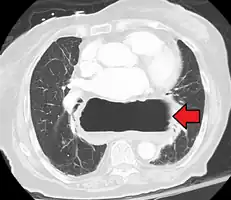

A hiatal hernia as seen on CT -

A large hiatal hernia as seen on CT imaging -